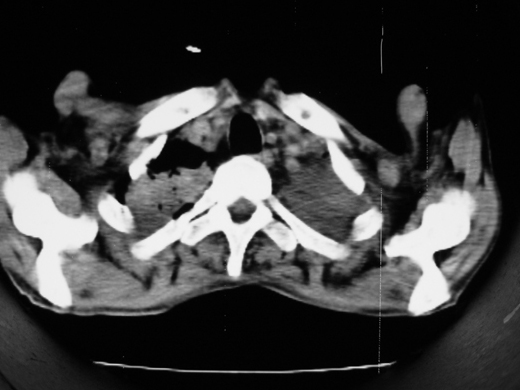

男69岁,年前胸片示肺感染治疗近一月今复查无明显好转,血象正常

双肺内不规则斑点状 片状及结节密实影,部分灶周见索条样影及\"树芽征\",左肺上叶实变,内见充气支气管影及斑状钙化,左侧少量胸腔积液,考虑1)双肺结核2)左侧胸腔积液

右肺多发片絮状结节状及时条索状影,左上肺实变,内可见虫蚀样空洞及支气管气象,左下肺片状及球形病灶,及胸腔积液征象,双肺病灶内多发钙化影,结合病史,考虑双肺继发型肺结核,左胸腔积液

右肺多发片絮状结节状及时条索状影,左上肺实变,内可见虫蚀样空洞及支气管气象,左下肺片状及球形病灶,及胸腔积液征象,双肺病灶内多发钙化影,上纵隔向左侧移位,结合病史,考虑双肺继发型肺结核,左胸腔积液。